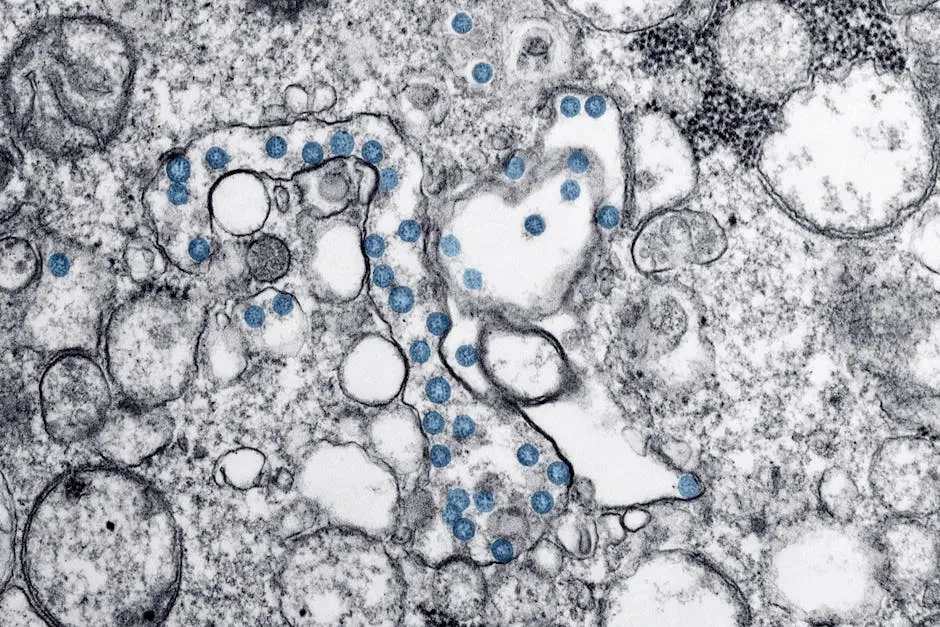

White blood cells are the key players in your immune system. They are made in your bone marrow and are part of the lymphatic system. White blood cells move through blood and tissue throughout your body, looking for foreign invaders such as bacteria, viruses, parasites and fungi. Imagine billions of tiny soldiers endlessly patrolling every highway and back road of your body, every single second of the day.

Bacteria or viruses that enter the body can be stopped right away by phagocytes, also known as scavenger cells. These special white blood cells enclose germs and “digest” them, making them harmless. The remains of the germs move to the surface of the phagocytes, where they can be detected by the adaptive immune system. That last part is crucial. It’s not just about killing the immediate threat. Your body is also learning from every attack, building intelligence for future battles.

5. Immunological Memory: Your Body’s Long-Term Intelligence System

This is honestly the most astonishing part of the whole system. Your immune system doesn’t just fight threats. It remembers them. The immune system keeps a record of every microbe it has ever defeated, in types of white blood cells known as memory cells. This means it can recognize and destroy the microbe quickly if it enters the body again, before it can multiply and make you feel sick.

During the first encounter with a pathogen, naïve T cells differentiate to effector T cells, which are able to mount an efficient and immediate immune response against the pathogen. Some effector T cells directly kill infected cells, while others, known as helper T cells, help immune cells mount a response, including stimulating B cells to secrete antibodies against pathogens and generate memory B cells. The whole system is incredibly coordinated, like a military force with specialists, generals, and intelligence officers all working in unison.

Perhaps the most important consequence of an adaptive immune response is the establishment of a state of immunological memory. Immunological memory is the ability of the immune system to respond more rapidly and effectively to pathogens that have been encountered previously, and reflects the preexistence of a clonally expanded population of antigen-specific lymphocytes. Think of it like your body keeps a filing cabinet with a profile on every enemy it has ever beaten. And those files? Adaptive immunity can provide long-lasting protection, sometimes for a person’s entire lifetime.